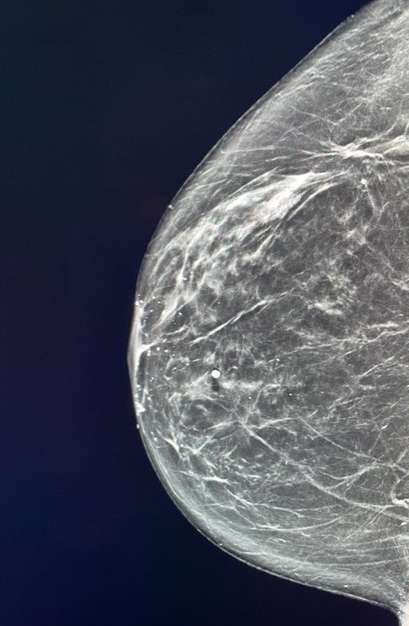

Case: Lymphoma of the Breast Figure 1

Right CC view of the breast shows a developing asymmetry in the lateral aspect of the right breast located 1 centimeter from the nipple. This was biopsy proven grade 2 follicular lymphoma.